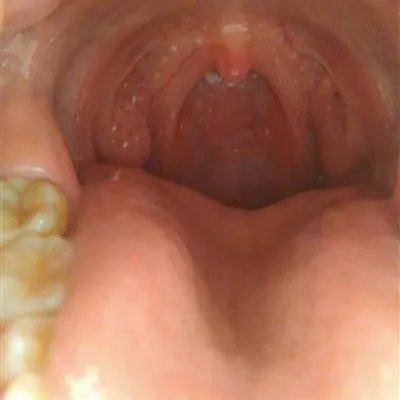

概述 许多人在生活中会有这样的疑惑,饮食方面也要特别注意,突然会感觉咽喉部很痒,有异物感,很难受,严重的如果治疗不及时还会出现呼吸困难,甚至还会导致窒息,其实这可能是过敏性咽喉炎在作怪。

过敏性咽喉炎最容易在季节交替的时候发病.比如春秋时节,很多人会对花粉过敏,有的人也对尘螨,真菌,动物毛屑等等产生过敏,所以患者要高度警惕,远离过敏源。那么,下面就请大家先来看看对于过敏性咽炎应该怎么治疗?方面的相关知识介绍吧。